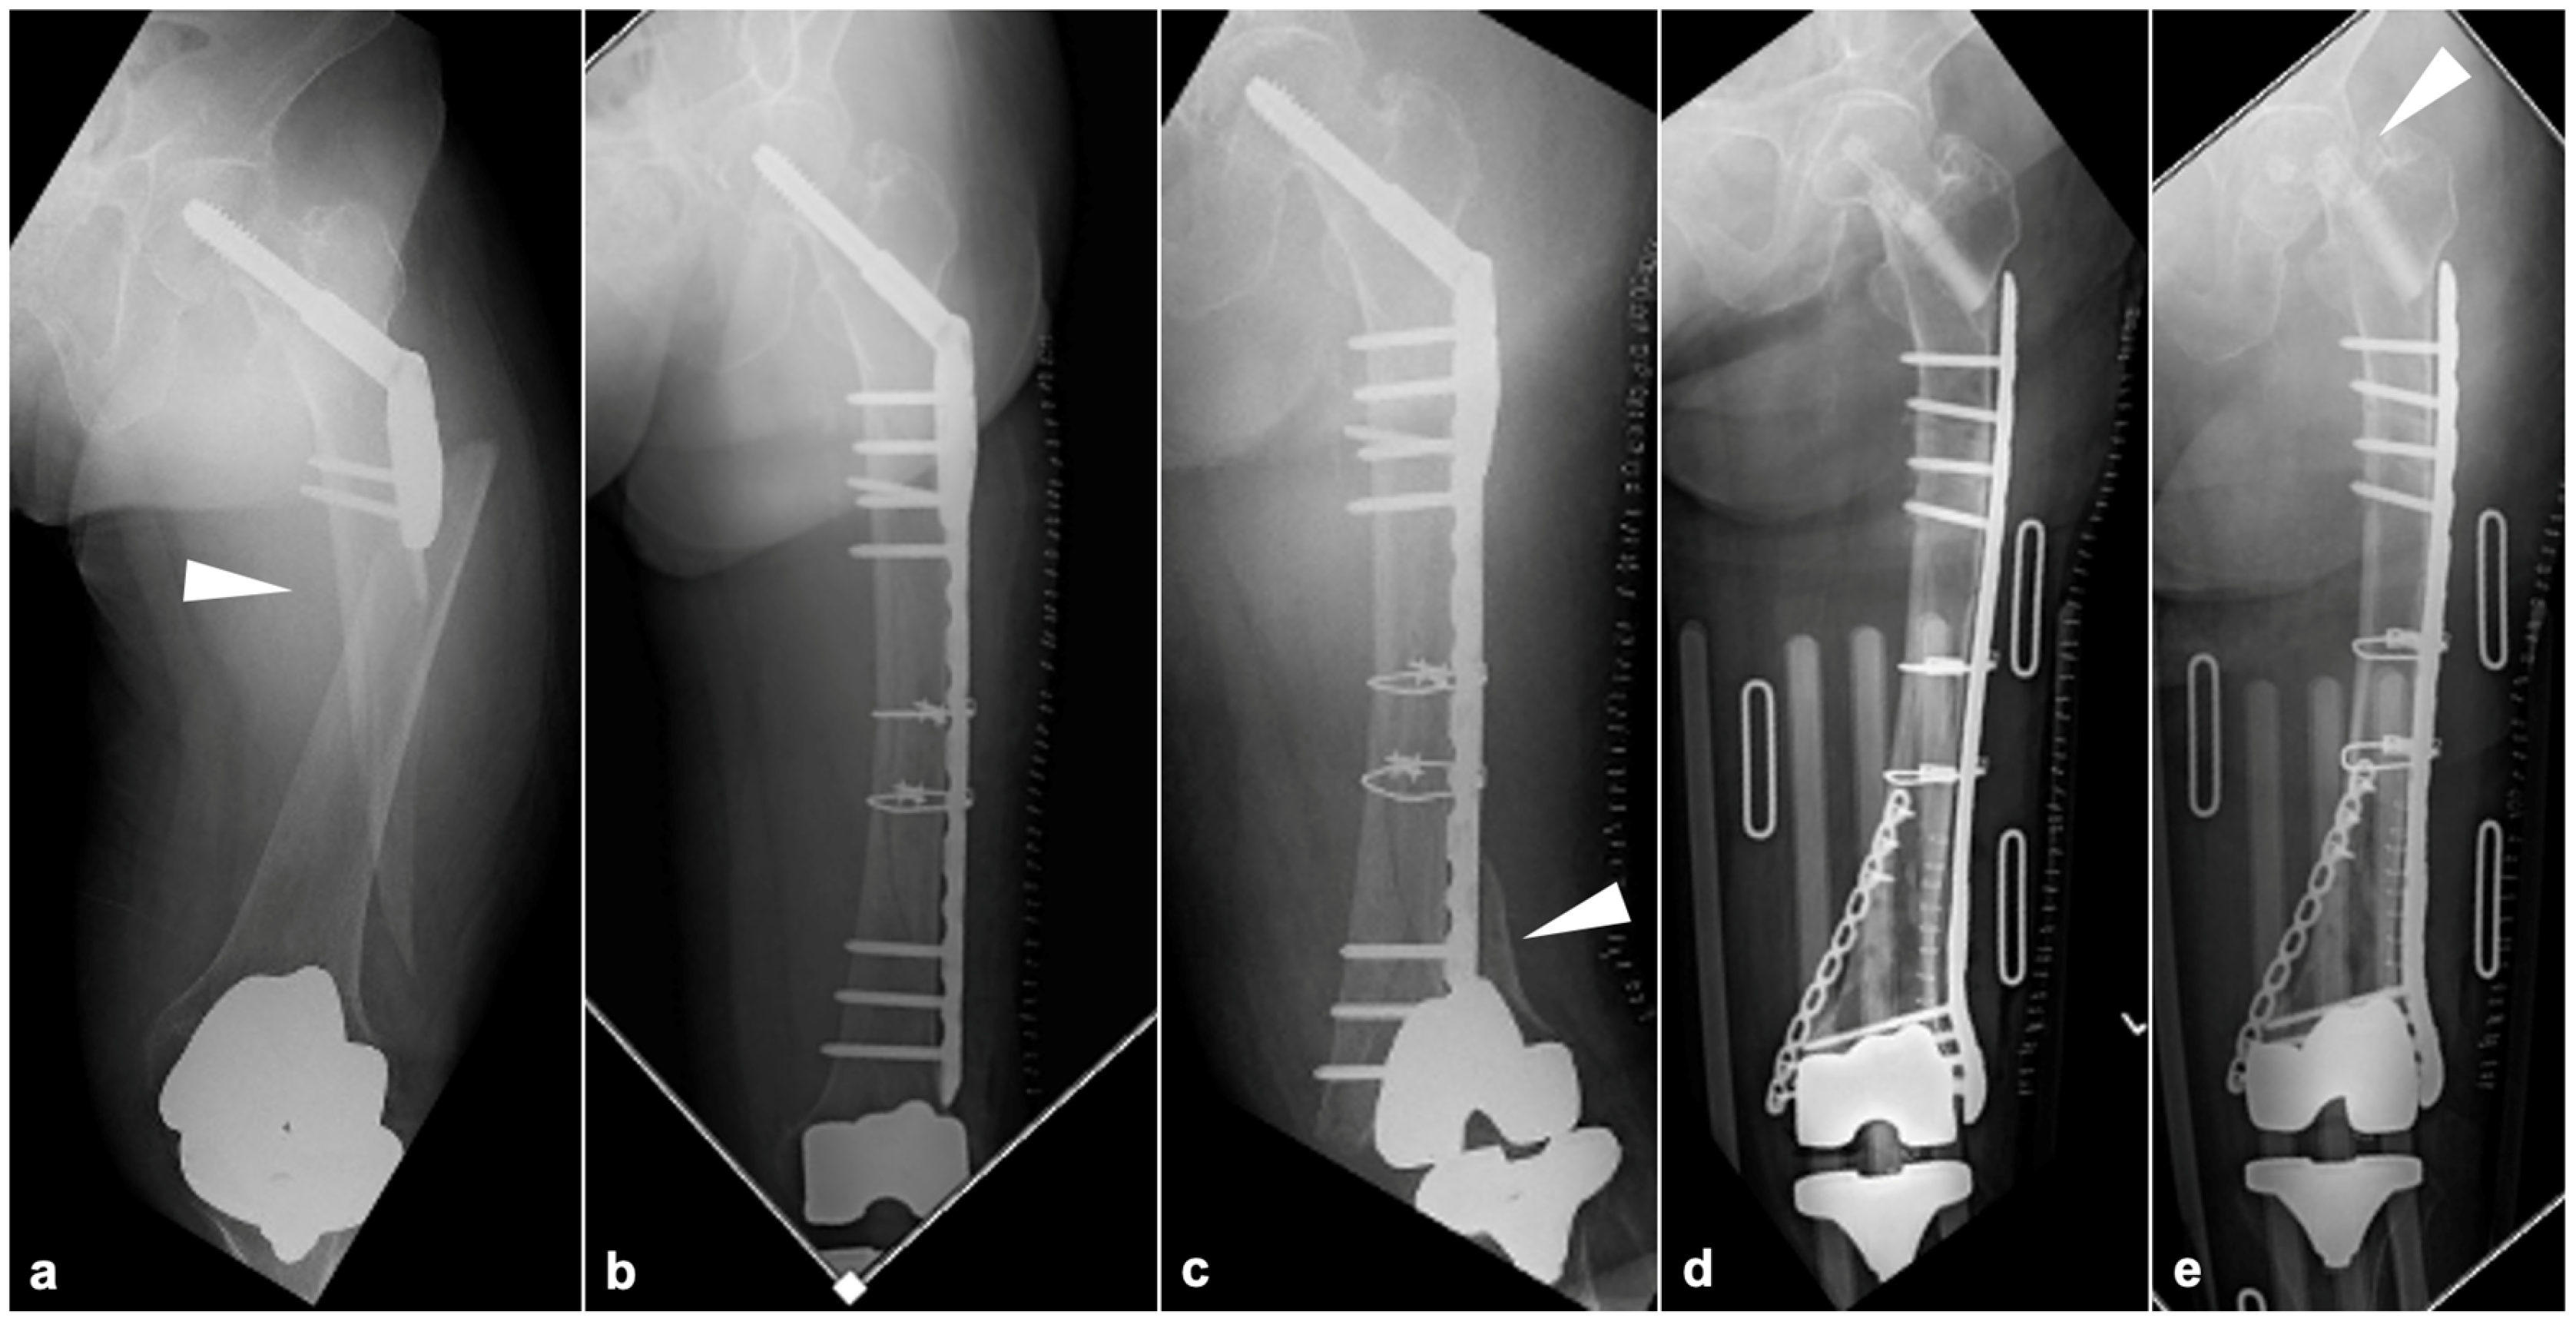

2.3.1. BHA/THA

2.3.3. TKA

3. Results